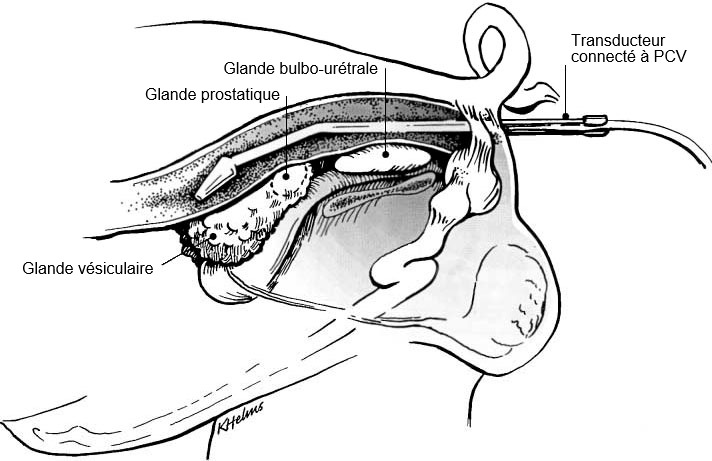

L'examen des glandes sexuelles accessoires doit être fait par voie transrectale en utilisant une sonde linéaire (Clark et Althouse, 2002; Figure 1), tandis que pour le testicule, l'épididyme et le cordon spermatique, un secteur ou sonde (micro) convexe est le type de dispositif préféré (figures 2A et B). On utilise des fréquences de 5,0 à 9,0 MHz, les plus basses étant les plus appropriées pour la plupart des tissus qui nécessitent une plus grande profondeur de pénétration (à savoir le testicule et le corps de l'épididyme) et les fréquences plus élevées pour les structures plutôt petites comme la tête et la queue de l'épididyme). Cela dépendra donc de l'objectif de l'examen et la fréquence sera alors optimale.

Figure 1: Positionnement du support du transducteur avec le transducteur droit pour la visualisation des glandes sexuelles accessoires du verrat (Clark & Althouse, 2002).